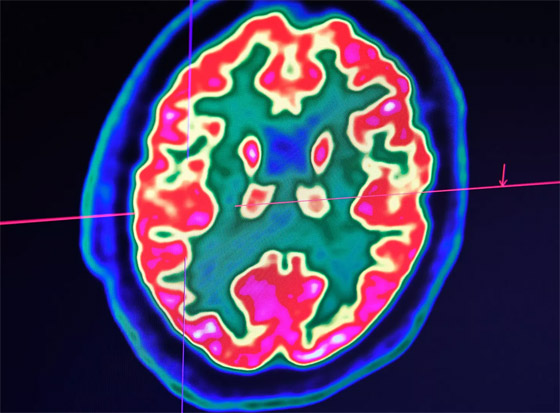

وزُرعت شريحتان دقيقتان في دماغ مريض ألماني، وفقاً للدراسة التي نشرها أوجوال تشودري ونيلز بيرباومر، وبعدها، تمكن المريض من تكوين كلمات وجمل كاملة باستخدام الإشارات العصبية الدماغية. وقد أجرى تشودري وبيرباومر تجارب مماثلة عامي 2017 و2019، ولكن تعرضت الدراستان للحذف.